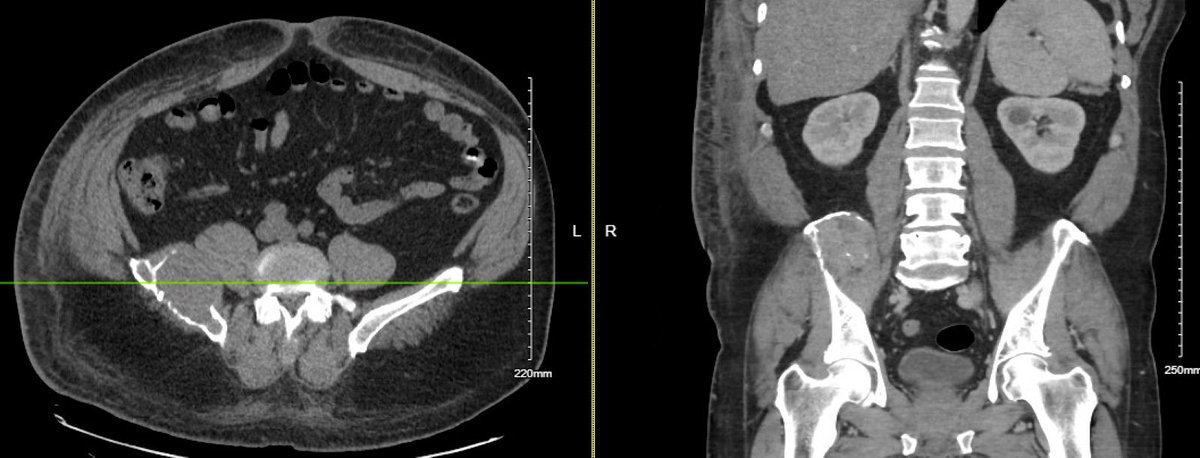

@ASanchez_PS I am seeing an homogenous mass around the right paraspinal area, infiltrating the bone. Wondering if it could be any soft tissue sarcoma???

@davserantes What I was thinking … IgG level almost 3000. Light chain ratio slightly off. Will update when SIFE comes back